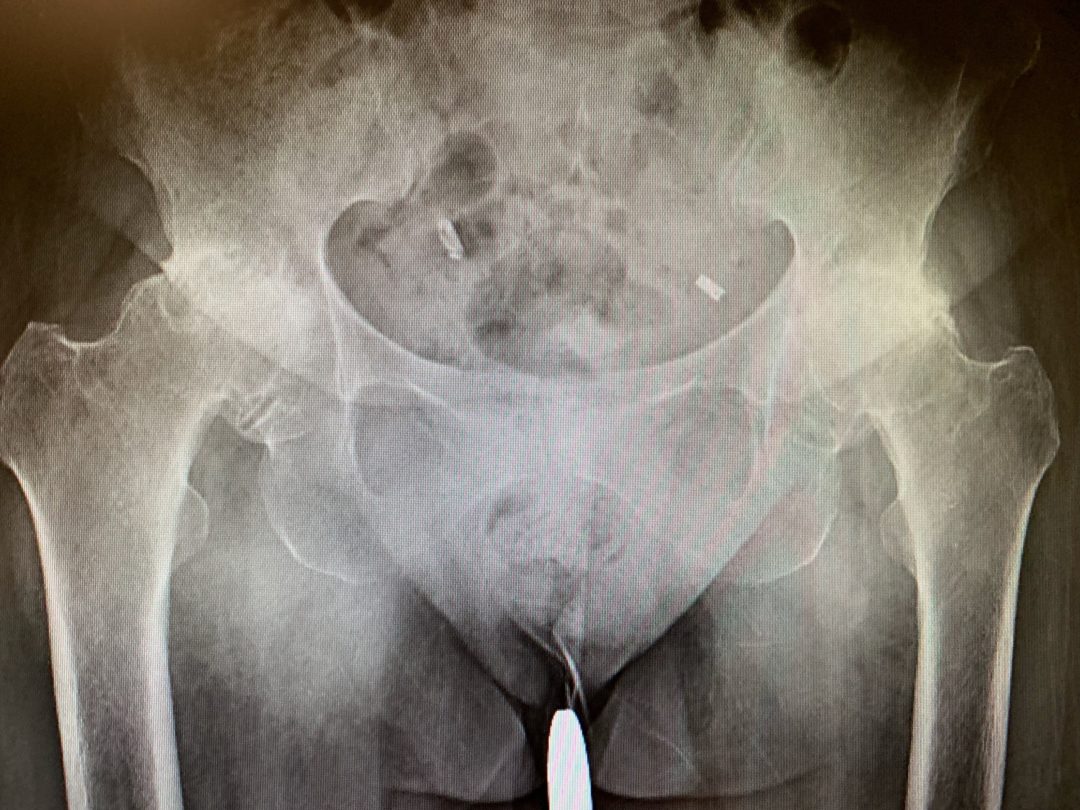

Case Study Bilateral Hip Replacement in a 65yearold Female

Case Study Bilateral Total Hip Replacement 65 yr. old female Hip Replacement Xray Female In a total hip replacement (also called total hip arthroplasty), the damaged bone and cartilage is removed and replaced with prosthetic components. Radiography is the primary imaging method for the evaluation of total hip arthroplasty. To perform a hip replacement, the surgeon: Radiography is the primary imaging method for the evaluation of hip arthroplasties, and imaging of a hip arthroplasty. Hip Replacement Xray Female.

Double hip replacement, Xray Stock Image C002/6531 Science Photo Hip Replacement Xray Female This overview focusses on the normal findings and complications of. Hip arthroplasties are a very common form of joint replacement for the treatment of different pathologic conditions of. The damaged femoral head is removed and replaced with a metal stem that is placed into the hollow center of the femur. It is performed primarily to relieve hip pain and stiffness. Hip Replacement Xray Female.